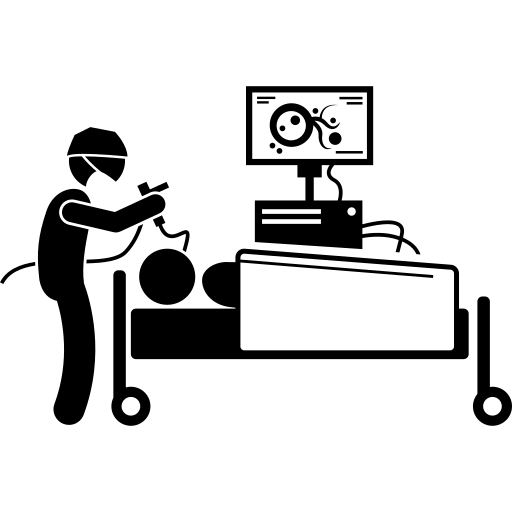

Se trata de un Curso Semipresencial de Ventilación Mecánica

Dado que los pacientes de UTI sometidos a la

ventilación mecánica invasiva son los que requerirán realizarse BAL como diagnóstico de

neumonías asociadas a la ventilación mecánica y que cada día que permanecen con la vía

aérea instrumentada, el riesgo aumenta, además de que, aquellos con destete prolongado

requerirán traqueostomía, que de realizarse por punción percutánea se puede guiar

mediante ecografía o broncoscopía y para la decanulación resulta ideal descartar

endoscópicamente lesiones anatómicas (estenosis, granulomas) o funcionales (trastornos

de la deglución, parálisis de las cuerdas vocales, etc), resulta de gran utilidad que el equipo

se encuentre disponible en la UTI. De los últimos 18 procedimientos 10 fueron realizados a

pacientes de UTI y, en un caso, un paciente de sala fue sometido al procedimiento en UTI

por falta de disponibilidad en quirófano, retornado el mismo día a la sala general.

Finalmente, se prevee realizar una capacitación para que los médicos de UTI adquieran

manejo básico de endoscopía respiratoria para: intubación dificultosa, valoración de la vía

aérea en paciente ventilados en forma prolongada, toma de muestras respiratorias, etc.